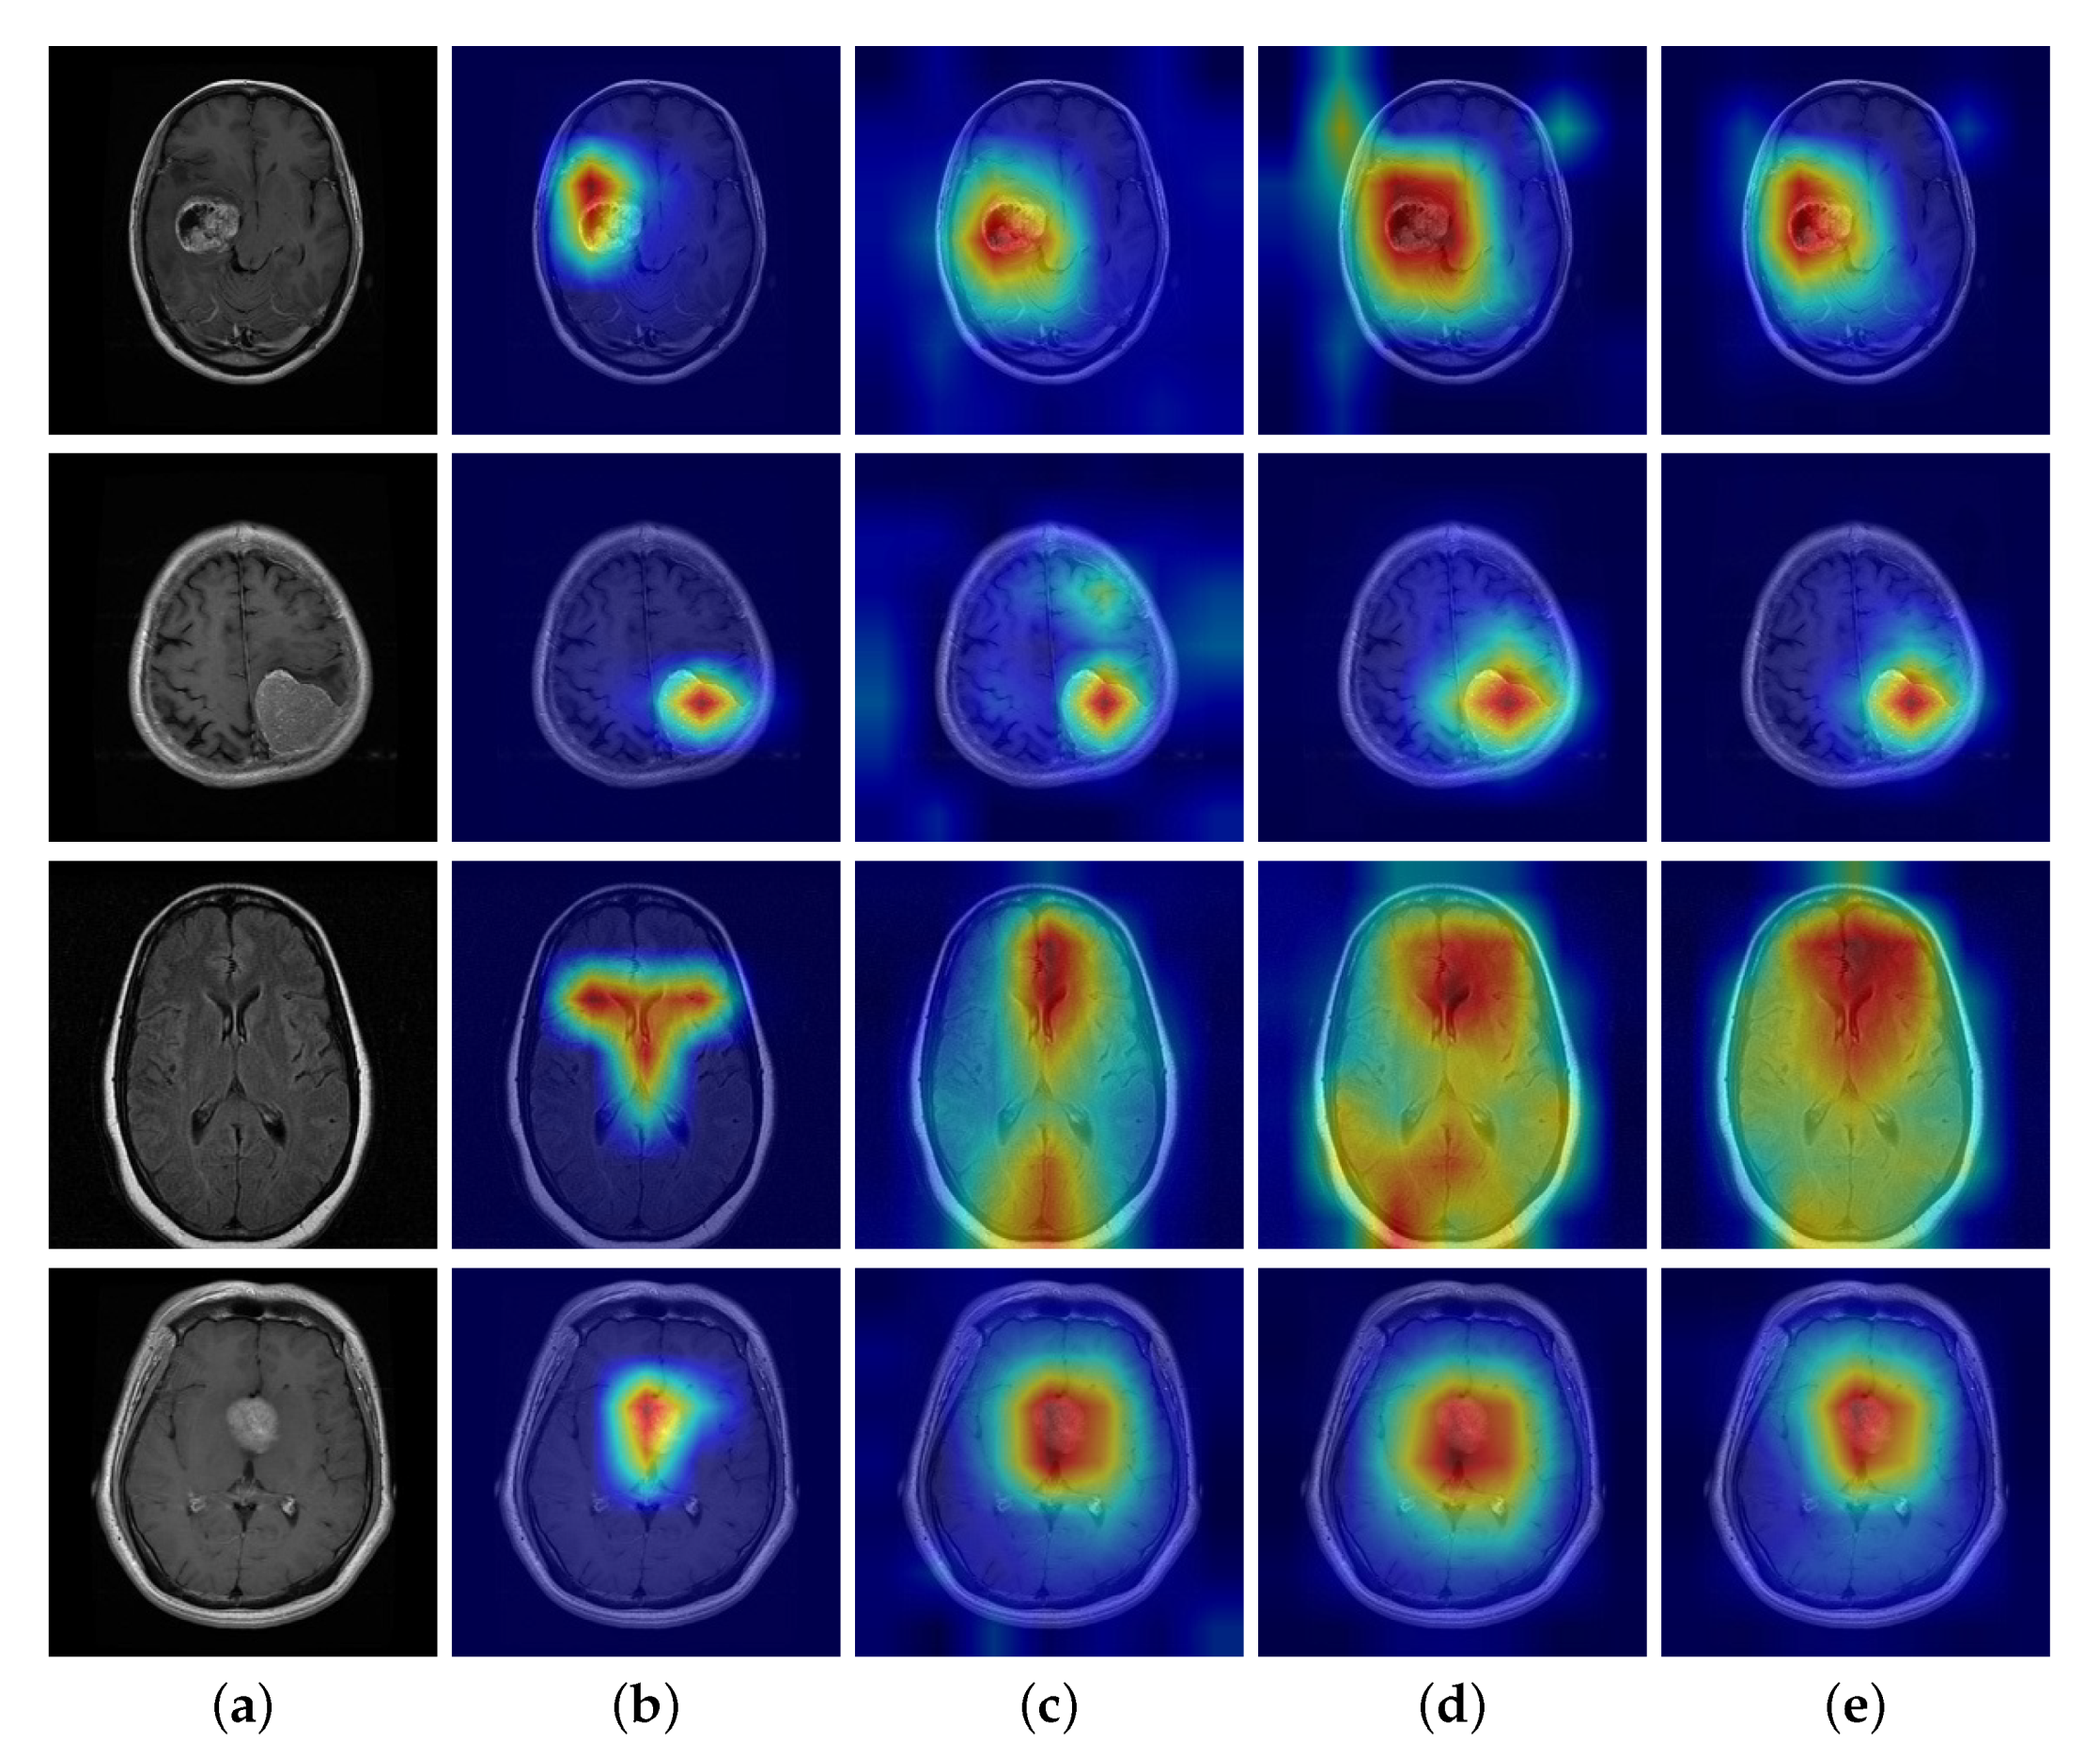

The DSE block uses an adaptive strategy harmony with the characteristics of brain tumor MRIs to guide the network in suppressing the interfering factors and extracting more informative features. The effect of the global orderless feature suppression (GS) strategy is quite different from that of the local spatial feature suppression (LS) strategy. In an attempt to clarify the working mechanism of each module, here we present a comparison between our method and the baseline by class activation map (CAM) observation, as shown in Figure 7.

Figure 7.

Class activation map (CAM) comparison with and without our modules in dataset BT-4C. Top to bottom: glioma, meningioma, normal, pituitary. (a) Original image, (b) CAM with GS module, (c) CAM without GS module, (d) CAM with LS module, (e) CAM without LS module.

Firstly, the GS module was introduced in CNN separately for discriminative localization using the GAP. The global feature is a set of abstract orderless encodes, in which some clues can unfold from CAM. Figure 7a illustrates that the network with GS prunes the CAM region compared to Figure 7b without GS. Specifically, when applying the BS strategy, the salient area of the CAM is clear even if there is no tumor in the MRI. In contrast, without BS, there is bit diffusion or worse for no-tumor MRIs. The explanation of the difference is that the network works the way we intended it to, being more concerned with distinct discriminative features from global encodes than background or texture ones.

Secondly, we processed the LS module in the same way to generate the CAM. As the local feature is an aggregation of spatial order information, it seemed more suitable for CAM to interpret what parts of the image are of interest to the network. Figure 7c,d shows that the LS module achieves an effect opposite to that of the GS. When applying the LS strategy, the CAM displays an extended salient area where the network pays more attention to the tumor and its associated parts. In contrast, without LS, there is a limited set of the salient region of spatial locations. This implies that the LS module helps the network excavate a more informative area, which is expected to improve classification performance.

The definition of all brain tumor types depends on the tumor size and the related parts involved in the brain [55]. That explains why the DSE block triggers two opposite effects, as the global orderless feature focuses on the tumor itself and the local spatial one concentrates on the associated part of the brain.